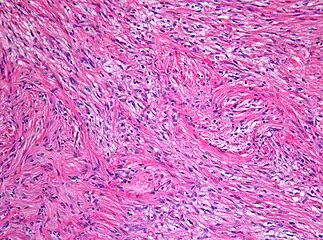

- Histopathology of pilocytic astrocytoma (grade I WHO).

Under the microscope, the tumor is seen to be composed of bipolar cells with long "hair-like" GFAP-positive processes, giving the designation "pilocytic" (that is, made up of cells that look like fibers when viewed under a microscope[6]). Some pilocytic astrocytomas may be more fibrillary and dense in composition. The presence of Rosenthal fibers,[7] eosinophilic granular bodies, and microcysts can often be seen. Myxoid foci and oligodendroglioma-like cells may also be present, though these are not specific to pilocytic astrocytoma. Long-standing lesions may show hemosiderin-laden macrophages and calcifications.